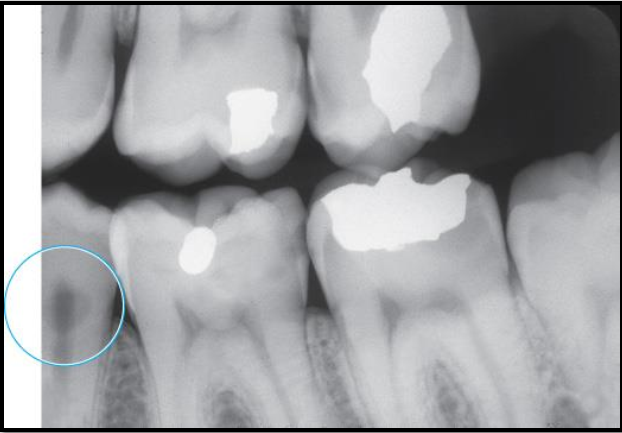

Identify the carious lesion.Â

Root surface cariesÂ

Describe the clinical and radiographic appearance of Root surface caries

Clinical → easily seen on exposed root surface; SAUCER-SHAPED; brownish colour; leathery texture

Radiographic → cupped-out or crater-shaped radiolucency; interproximal just below CEJ